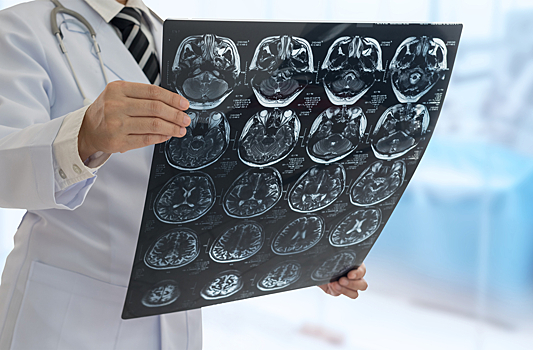

В рамках работы специалисты проанализировали состояние пациентов с раком мозга, в том числе, до постановки диагноза.

В частности, перед диагнозом пациенты отмечали у себя внезапно возникшие проблемы с памятью, невнятность речи, неустойчивость при ходьбе. Кроме того, у многих ухудшалось зрение. Такие симптомы должны насторожить, предупредили медики.

Доля злокачественных опухолей оценивается примерно в 30%. Самая опасная опухоль — глиобластома, которая может возникать сразу в форме четвертой степени злокачественности.